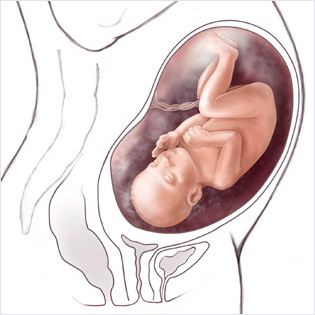

Doğum için en önemli olanlar anne, bebek ve yoldur. Çatısı dar olmak ne demek diyenler için şöyle yazalım, Çatı dediğimiz doğum kanalına girişindeki yol kastedilir. Çatım dar normal doğum olur mu diye sorduğunuzu duyar gibiyim meleklerim. Buna siz değil malesef doktor karar verecek. Çatım dar nasıl anlarım da diyen kadınlarımız olabilir bu ancak doğumda anlaşılır kızlar. Bunu da doktorlar belirleyecekler. Doğum başladığında örneğin size normal doğum demiş olabilirler ama hoop sezeryana alınıyor olabilirsiniz.

Kadınların kimilerinde bebeğin geçiş yolu uygun genişlikte, kimilerinde de bu kanal, dar olabilmektedir. Tabii bu darlığın derecesi değişmektedir. Darlık ileri derece de, bebeğin geçmesine engel olabilecek durumda ise vajinal doğum gerçekleşemez ve sezaryene başvurulur.

Pelvis muayenesi yani diğeri adı ile çatı muayenesi bebek başının, geçtiği yol yani pelvise olan uyumuna bakılmaktadır. Doktorlar bu muayene ile yaklaşık tahmin ederler. Genetik bütün özelliklerine bu muayenede bakarlar.

Bebeğin iri ve duruş pozisyonuna bağlı olarak doktorda size doğum şekli nasıl olması gerektiğine dair tavsiye verir. Eğer pelvik muayenede çatı darlığı (pelvik darlık) olduğuna yani doğum yolunun normal doğuma imkan vermeyecek derecede dar olduğuna karar verilirse normal doğum hiç denenmeden sezaryen ameliyatı planlanır. Ancak bu her zaman mümkün olmaz, yani çatı muayenesi her zaman doğum şeklini kesin belirleyemeyebilir bu durumda normal doğum denenir ve doğumun ilerlemesi esnasında yapılan muayeneler ile daha net karar verilebilir.

Doğum sırasında rahim ağzı açık olduğu için hem rahim ağzının açılma miktarı ve durumu hem de bebeğin kafasının pozisyonu, durumu değerlendirilebilir bu nedenle doğum esnasında yapılan çatı muyenesi daha net bilgi verir. Ancak doğumdan önce gebeliğin son haftalarında yapılan çatı muayenesi de ön fikir vermesi için ve belki de normal doğum yapamayacak hastalaların normal doğum denenmeden farkedilmesi için gereklidir.

Doğum için en önemli olanlar anne, bebek ve yoldur. Çatısı dar olmak ne demek diyenler için şöyle yazalım, Çatı dediğimiz doğum kanalına girişindeki yol kastedilir. Çatım dar normal doğum olur mu diye sorduğunuzu duyar gibiyim meleklerim. Buna siz değil malesef doktor karar verecek. Çatım dar nasıl anlarım da diyen kadınlarımız olabilir bu ancak doğumda anlaşılır kızlar. Bunu da doktorlar belirleyecekler. Doğum başladığında örneğin size normal doğum demiş olabilirler ama hoop sezeryana alınıyor olabilirsiniz.

Kadınların kimilerinde bebeğin geçiş yolu uygun genişlikte, kimilerinde de bu kanal, dar olabilmektedir. Tabii bu darlığın derecesi değişmektedir. Darlık ileri derece de, bebeğin geçmesine engel olabilecek durumda ise vajinal doğum gerçekleşemez ve sezaryene başvurulur.

Pelvis muayenesi yani diğeri adı ile çatı muayenesi bebek başının, geçtiği yol yani pelvise olan uyumuna bakılmaktadır. Doktorlar bu muayene ile yaklaşık tahmin ederler. Genetik bütün özelliklerine bu muayenede bakarlar.

Bebeğin iri ve duruş pozisyonuna bağlı olarak doktorda size doğum şekli nasıl olması gerektiğine dair tavsiye verir. Eğer pelvik muayenede çatı darlığı (pelvik darlık) olduğuna yani doğum yolunun normal doğuma imkan vermeyecek derecede dar olduğuna karar verilirse normal doğum hiç denenmeden sezaryen ameliyatı planlanır. Ancak bu her zaman mümkün olmaz, yani çatı muayenesi her zaman doğum şeklini kesin belirleyemeyebilir bu durumda normal doğum denenir ve doğumun ilerlemesi esnasında yapılan muayeneler ile daha net karar verilebilir.

Doğum sırasında rahim ağzı açık olduğu için hem rahim ağzının açılma miktarı ve durumu hem de bebeğin kafasının pozisyonu, durumu değerlendirilebilir bu nedenle doğum esnasında yapılan çatı muyenesi daha net bilgi verir. Ancak doğumdan önce gebeliğin son haftalarında yapılan çatı muayenesi de ön fikir vermesi için ve belki de normal doğum yapamayacak hastalaların normal doğum denenmeden farkedilmesi için gereklidir.